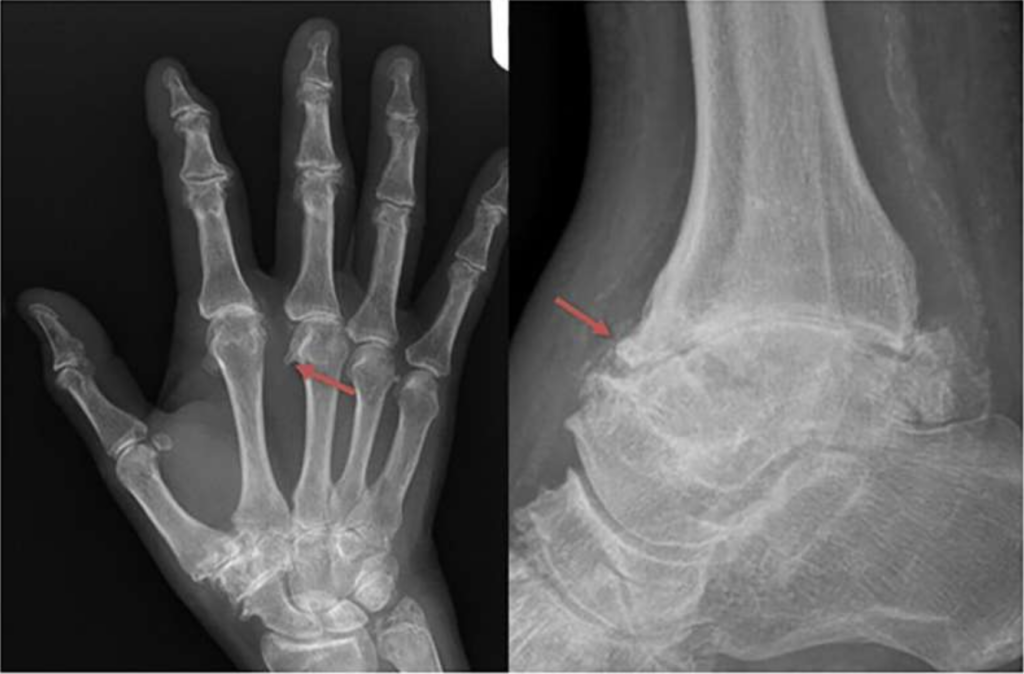

Haemochromatosis arthropathy is a complication associated with haemochromatosis that most commonly affects the joints of the hands, but also the knees, ankles, and hips. Despite its impact, it has long lacked a formal classification. The European Alliance of Associations for Rheumatology (EULAR) task force has now developed the first classification criteria for haemochromatosis arthropathy, which were presented by Prof. Patrick Kiely during the EULAR Congress held in Barcelona on 14 June 2025. A score of 5 out of 11 effectively distinguishes haemochromatosis arthropathy from similar conditions such as osteoarthritis and calcium pyrophosphate deposition disease (CPPD), with high specificity. These criteria will support future research and improve recognition of this condition. The criteria are summarised in the following table.

‘The European Alliance of Associations for Rheumatology—has developed the first classification criteria for hemochromatosis arthropathy (HA) from a unique derivation cohort using rigorous methodology. HA is distinctive arthropathy associated with genetic hemochromatosis—a condition where iron levels build up over time. This has many consequences, including liver cirrhosis, diabetes, and a distinctive arthropathy. [..]’